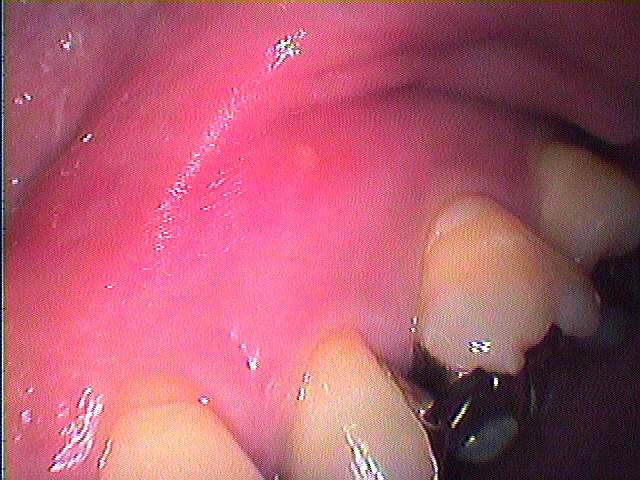

頬側にわずかにフィステル用のものができています

当医院で根の治療したのですが、、、、

薬も先まで入っていますが、、、、

違和感がずっとあるとのこと

頬側を開け、病巣をソウハを行い骨補填剤を入れることになりました